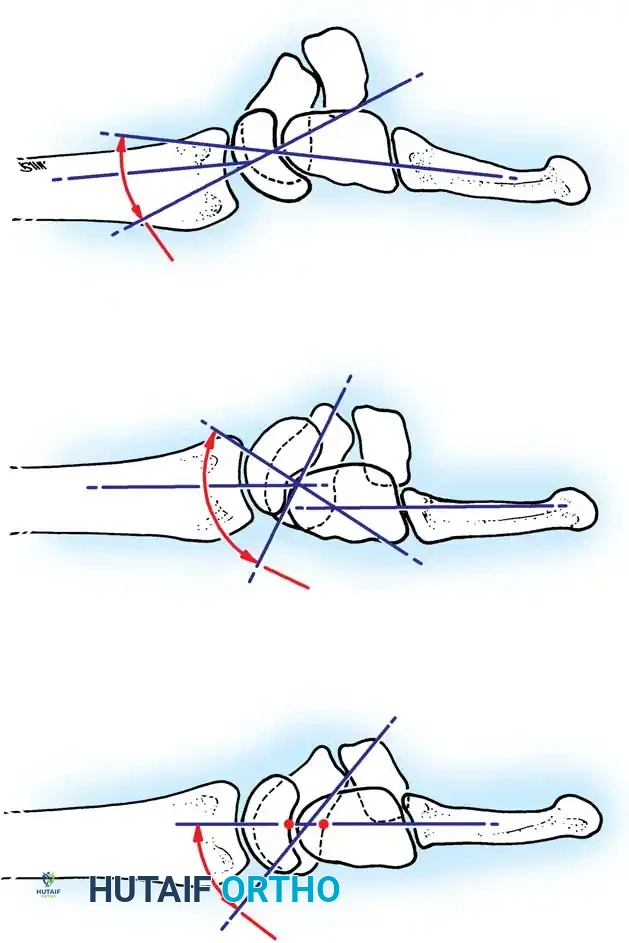

Linscheid et al. emphasized the critical importance of the true lateral radiograph. In a normal wrist, the longitudinal axes of the radius, lunate, capitate, and third metacarpal should be collinear within an approximately 15-degree tolerance.

When ligamentous disruption occurs, predictable collapse patterns emerge:

1. Dorsal Intercalated Segment Instability (DISI): The distal articular surface of the lunate tilts to face dorsally. This is the hallmark of scapholunate dissociation.

2. Volar Intercalated Segment Instability (VISI): The distal articular surface of the lunate tilts toward the palm. This is typically associated with lunotriquetral dissociation.

Fig. 66-77 A, Normal scapholunate and capitolunate angles. B, DISI deformity. C, VISI deformity.

4. DISI Deformity: On the lateral view, the normal scapholunate angle is 30° to 60° (mean 47°), and the capitolunate angle is <20°. In a DISI deformity, the scapholunate angle exceeds 60° (often >80°), and the capitolunate angle exceeds 20°.